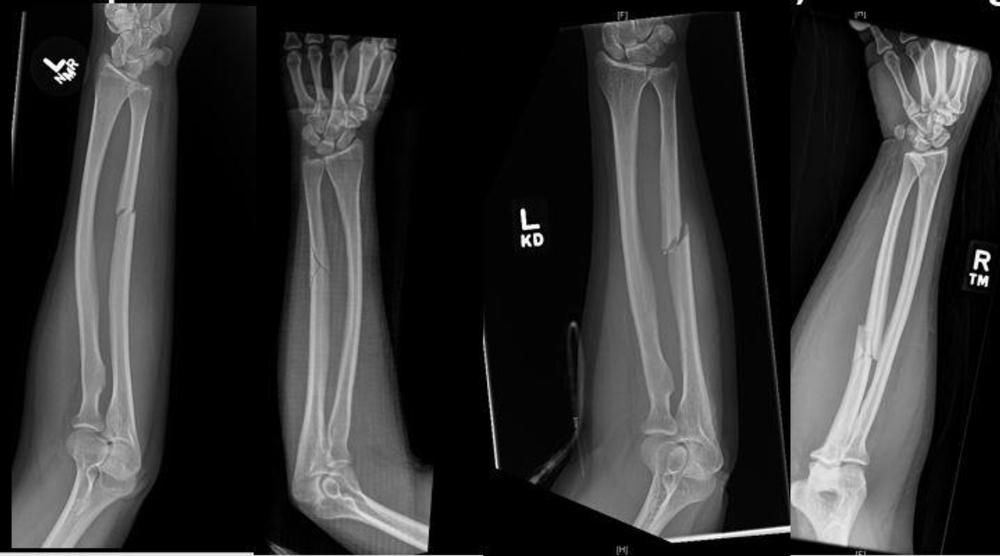

Figure 2. X-ray shows fracture to the ulna bone of the forearm.

Fractures to the ulna, the bone on the pinkie side of the forearm, often occur when people hold up their hands to protect their faces from being struck with an object. These breaks are referred to as “nightstick fractures,” because they are frequently seen in people who try to block blows from nightsticks wielded by police officers.

Analysis of the radiographs demonstrated that intimate partner violence was strongly associated with minimally displaced fractures.

“The radiological characteristics we were looking at were the location of the fracture, the pattern of the fracture in terms of how it broke, and the displacement of the fracture,” said study lead author David Sing, M.D., an orthopedic surgery resident at Boston Medical Center. “Out of all those things, what we usually saw was a minimally displaced fracture, meaning the bone is broken all the way through but has not shifted significantly.”

“It’s actually rare to break your ulna in a fall,” Dr. Khurana said. “If a radiologist is seeing an ulnar fracture that is non-displaced, and the woman says she had a fall, it’s actually quite concerning for intimate partner violence.”